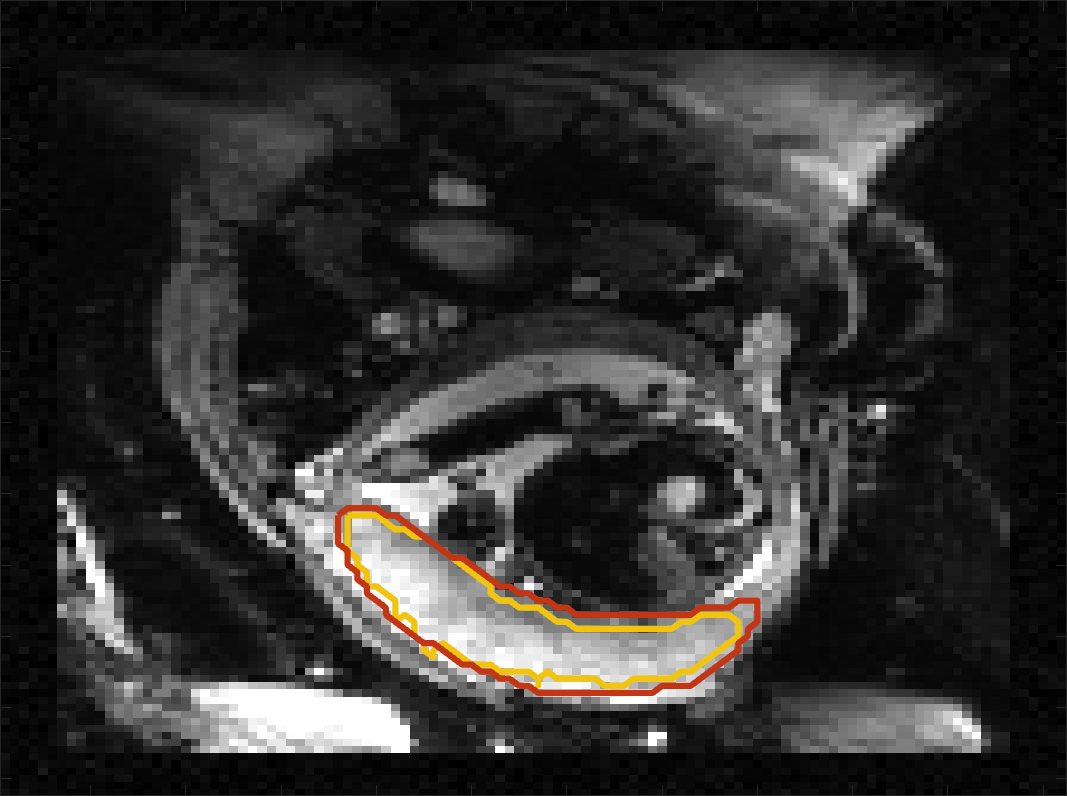

Figure 4 compares the predicted label maps with ground truth on subjects with increasing Dice scores using the BW-CE model. The model accurately identifies the location of the placenta, but in the worst cases misses boundary details.

BOLD Time Series Evaluation

Figure 5 presents example predicted segmentations at multiple points in the BOLD MRI time series for subjects. The predicted segmentations are robust to large fetal deformations and placental signal changes. Figure 6 (top) presents distributions of Dice score between predicted label maps of consecutive frames in the BOLD time series for all subjects in the test set. Distributions have high medians (Dice ) for all but one case, with high density at high Dice scores (Dice ). Dice differences are highly affected by fetal and maternal motion that cause placental deformation. We visually verified that modest drops in Dice () were mainly due to fetal motion, but subjects had a small number of frames with large drops (Dice ) that were caused by errors in the produced label maps. Figure 6 (bottom) shows D models of failed segmentations from two subjects from frames with Dice . Our model omitted parts of the placenta for Subject and added a large region for Subject . In practice, these failures ocurred in a small number of frames, of frames for Subject and of frames for Subject . Overall, predicted label maps are consistent between consecutive volumes of the MRI time series, achieving a Dice of and a BOLD difference of . The small differences between the relative mean-BOLD values suggest these produced segmentations may be suitable for research studies assessing placental function.